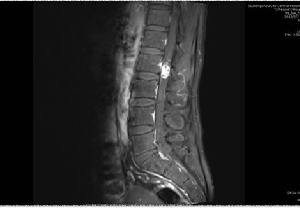

我院神經(jīng)外科顯微鏡下成功切除椎管內(nèi)腫瘤1例

日前,神經(jīng)外二科成功為一名腰2椎管內(nèi)占位性病變患者實施了顯微鏡下椎管內(nèi)病變切除術(shù),術(shù)后患者癥狀完全改善?;颊呃钅?,男,40歲,因“右下肢疼痛、麻木8年余,伴腰